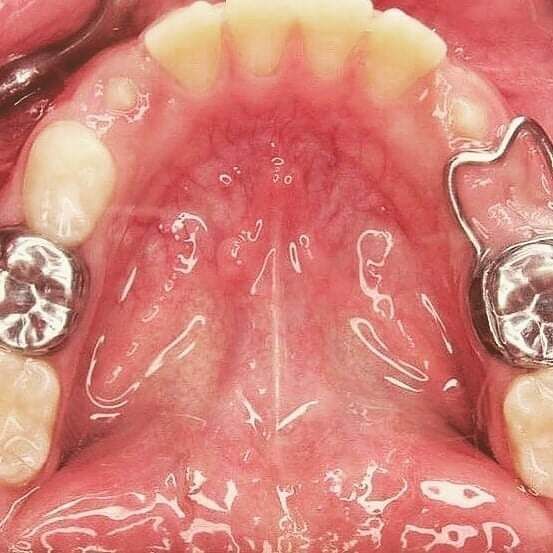

Manejo de Hábitos Dentales:

Corregimos hábitos dañinos como:

- Uso prolongado del chupón.

- Succión del pulgar.

- Otros hábitos que afectan el desarrollo maxilofacial.